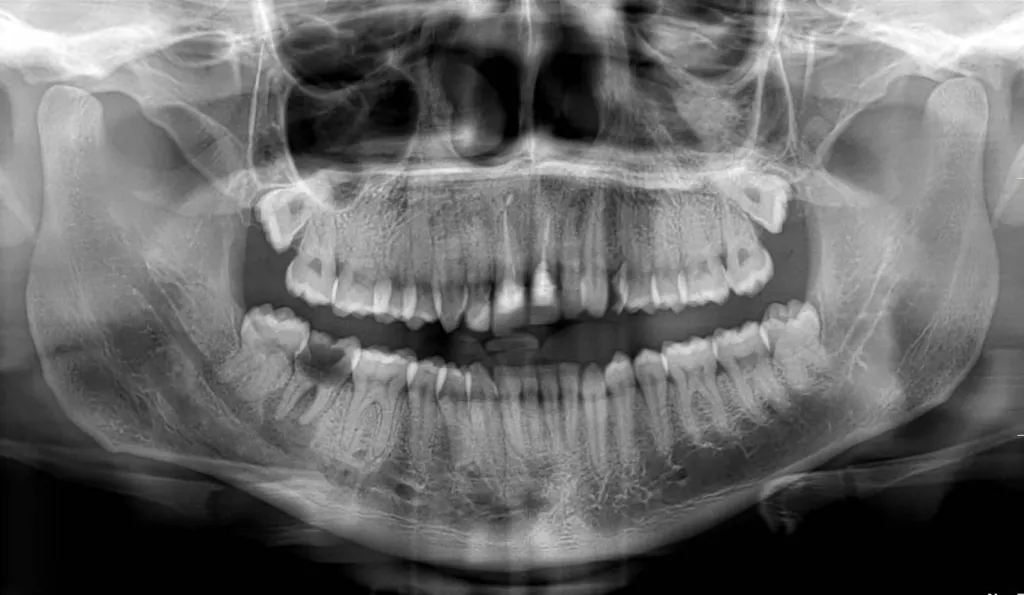

Le panoramique dentaire, ou OPG (orthopantomogramme), est un examen radiologique qui permet de visualiser en une seule image l’ensemble des dents, des mâchoires et des articulations temporo-mandibulaires. Réalisé dans un appareil à rayons X, il est indispensable pour le diagnostic bucco-dentaire, la préparation d’un traitement orthodontique ou la pose d’implants.

La radiographie panoramique dentaire permet de réaliser une imagerie de la totalité de la dentition ainsi que des mâchoires. Elle permet de connaître le positionnement des dents ainsi que les éventuelles anomalies au contact des racines et au niveau des couronnes. Elle permet de mettre en évid...